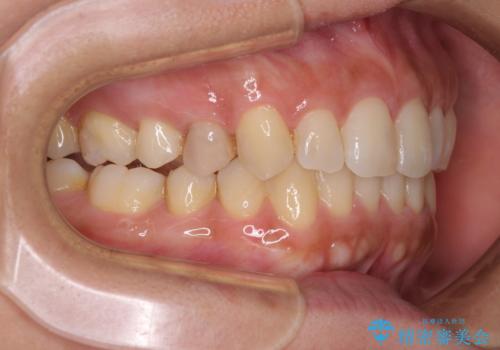

沖縄から飛行機で通院 インビザラインによる矯正治療

- 30代女性

- インビザライン

- 3年8ヶ月

- 定期的に東京に来るので、沖縄から矯正治療で通院したいとのことで来院された患者様です。

歯列不正は軽度であったので、応急処置の少ないインビザラインにて矯正治療を行うこととしました。

通院途中に、仕事の都合で東京に来る機会が激減してしまったため、なかなか治療が進まず、当初終了予定であった時期が2年近くずれ込んでしまいました。

今後もむし歯治療が必要となるため、日程を調整して沖縄から通院されるとのことでした。